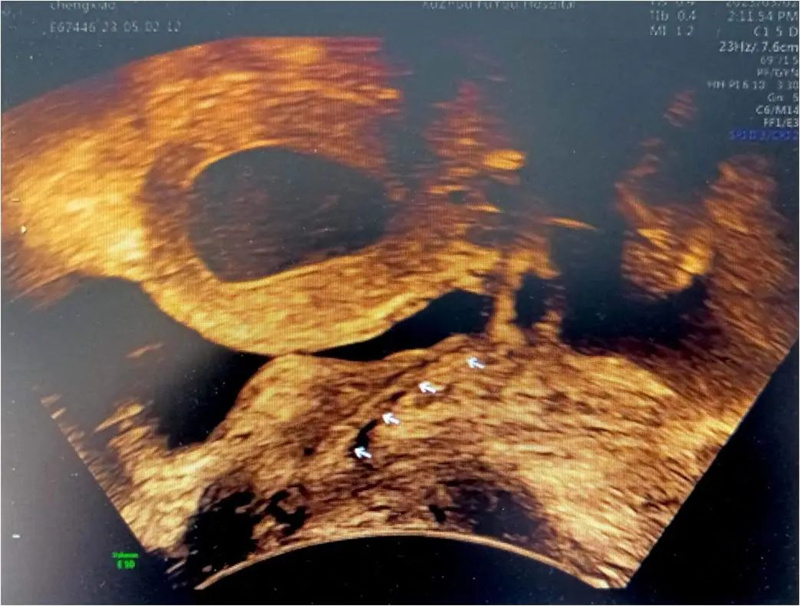

小玲(化名)13岁,到徐州市妇幼保健院就诊时,周期性腹痛已持续一年之久,不仅影响了孩子的学业、整个家庭也陷入了无限的困境。经各项检查发现,小玲患有先天梗阻性生殖道发育异常,先天性无阴道和条索状宫颈。虽然如此,小玲的子宫却发育良好,所以每次月经来潮时,经血无法正常排出,只能通过输卵管逆流到盆腔,导致难以忍受的腹痛。小玲也曾在父母的陪同下到国内多家大医院就诊,给出的治疗方案均是切除子宫体,等待时机做二期阴道成形手术,这对于一个13岁的女孩,还有父母来说是难以接受的。

早在进行前期检查时,李教授就发现小玲一侧输卵管因经血逆流造成严重积水伞端封闭,已失去了保留价值。如果能将积水的输卵管休整后移植到子宫下端代替宫颈管,便能变废为宝。但国内、外关于先天性阴道、宫颈发育异常的Ⅱ型阴道闭锁保留子宫的手术成功案例十分罕见,可参考的资料更是少之又少。国内、外文献检索亦未见有使用输卵管代替宫颈管的案例报道,也是李桂林教授团队在医学未知领域的又一次“创新之旅”。

在获得家属知情同意后,2023年4月底,通过腹腔镜方式,李桂林教授团队截取了3公分有血供和功能的输卵管,成功为小玲实施了输卵管代宫颈管+阴道成型重建手术。成为医学史上,国内、国际第一例成功实施该方案的病例。